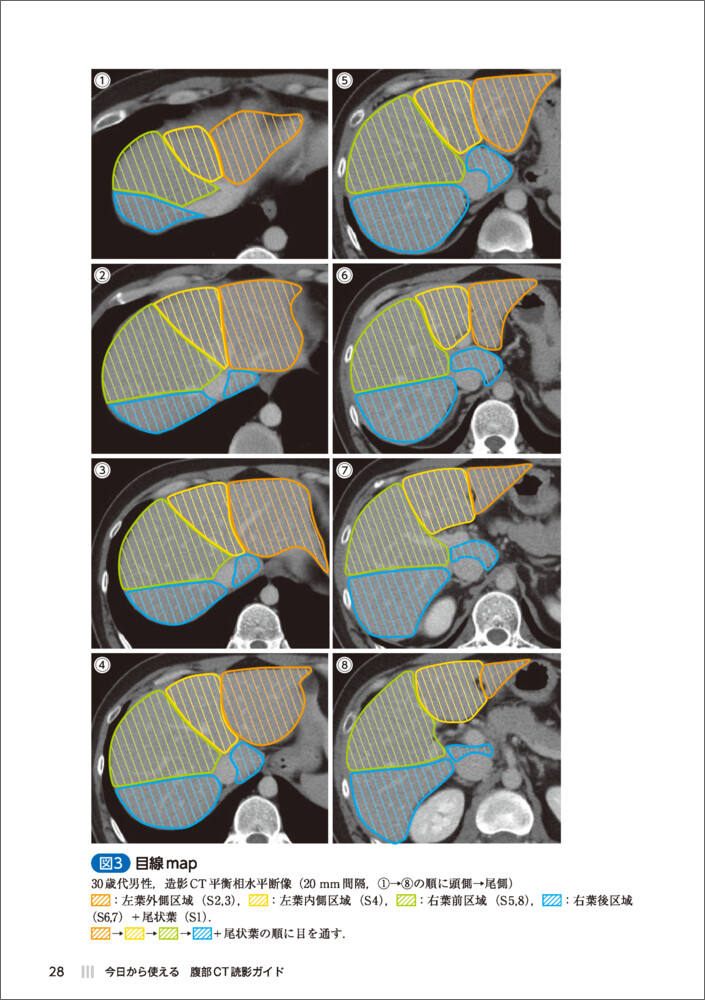

第1章 肝臓の歩き方

▶ 解剖 ▶ 目線map